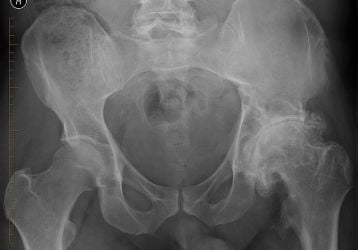

Эндопротезирование тазобедренного сустава: цена и условия

Операция на тазобедренный сустав — эндопротезирование. Стоимость операции в Москве и Санкт-Петербурге. Подготовка, длительность, ход. Видео.